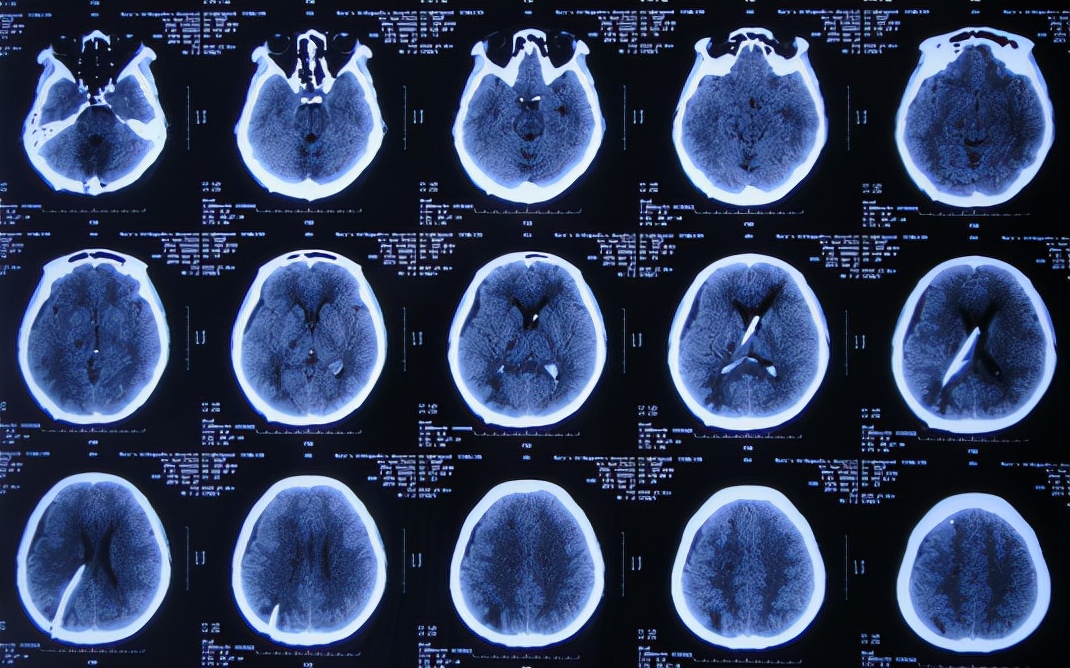

脑出血脑室外引流术后次日即2019年2月19日,复查头颅CT示出血未见明显减少( 图-3 )。

图-3: 2019年2月19日头颅CT

但脑出血脑室外引流术3天即2019年2月21日,出现尿崩症状,查头颅CT示脑室仍有出血( 图-4 );给予口服弥凝2天后症状好转,查血电解质示低钠、低钾,但给予积极纠正但效果仍不理想。

图-4: 2019年2月21日头颅CT

脑出血脑室外引流术7天即2019年2月25日,查头颅CT示出血明显好转( 图-5 )。

图-5: 2019年2月25日头颅CT

脑出血脑室外引流术12天即2019年3月2日,查头颅CT示出血完全消失,但脑室稍有扩大( 图-6 )。

图-6: 2019年3月2日头颅CT